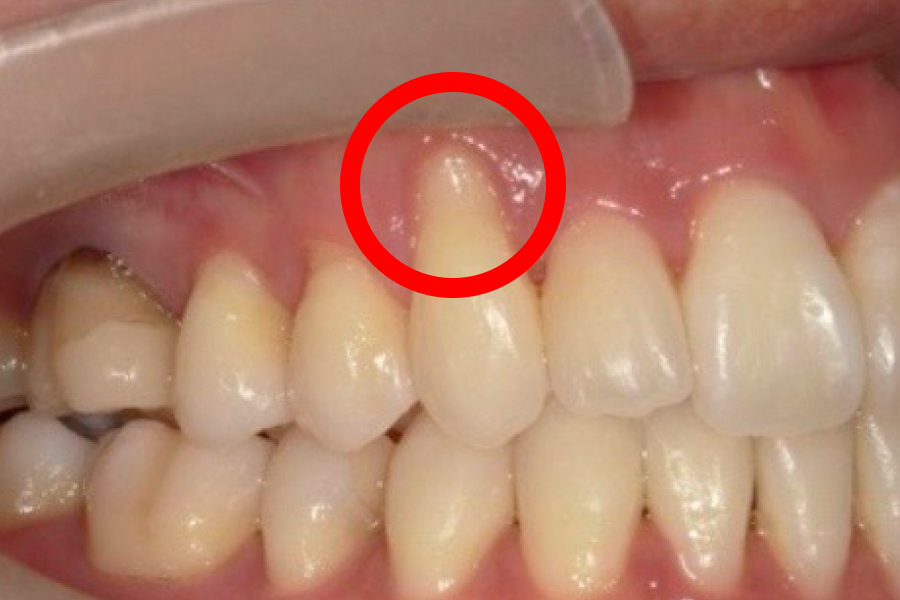

歯肉退縮が進むと、まず歯ぐきが下がって本来覆われていた根元が見えるため歯が長く見えるようになり、ついで歯根が露出することで冷水やブラッシングでしみる知覚過敏や根元のむし歯(歯根う蝕)、歯間が広がって食片が挟まりやすい・黒三角が目立つといった審美面の問題が生じます。

上顎の口蓋(こうがい)などから患者さま自身の結合組織を小さく採取し、歯肉退縮部の歯ぐきの内側に移植して露出した歯根を覆う治療です。歯ぐきの厚みと付着を増やすことで、これ以上の後退を抑え、知覚過敏の軽減や歯根う蝕(根元のむし歯)の予防にもつながります。移植片は縫合で固定し、治癒とともに周囲組織と一体化して安定していきます。

歯茎下がり症例